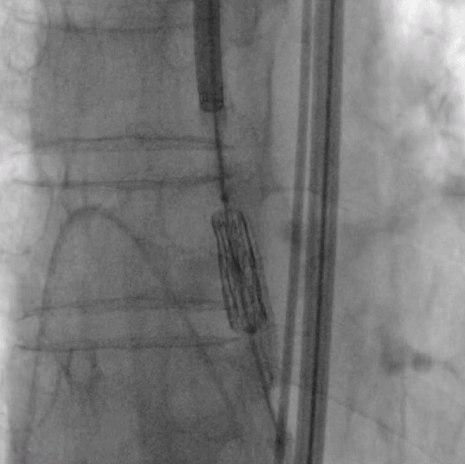

外周血管

瓣膜释放 主动脉根部造影